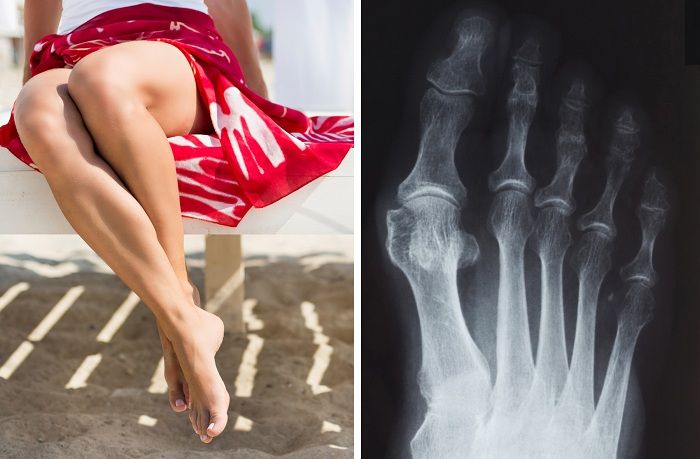

Вальгусная деформация стопы. Причины заболевания, его симптомы и лечение